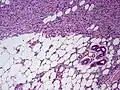

| Histopathological image of dermatofibrosarcoma protuberans. Local recurrence long after the first excision. H&E stain | |

-

Subcutaneous tissue infiltration (i.e. "honeycomb" growth pattern)

Monotonous, plexiform structure of tumour

DFSP formed both by fibroblastic and histiocytic elements

Hemosiderin deposits beneath the tumour

Immunostain positive for CD34